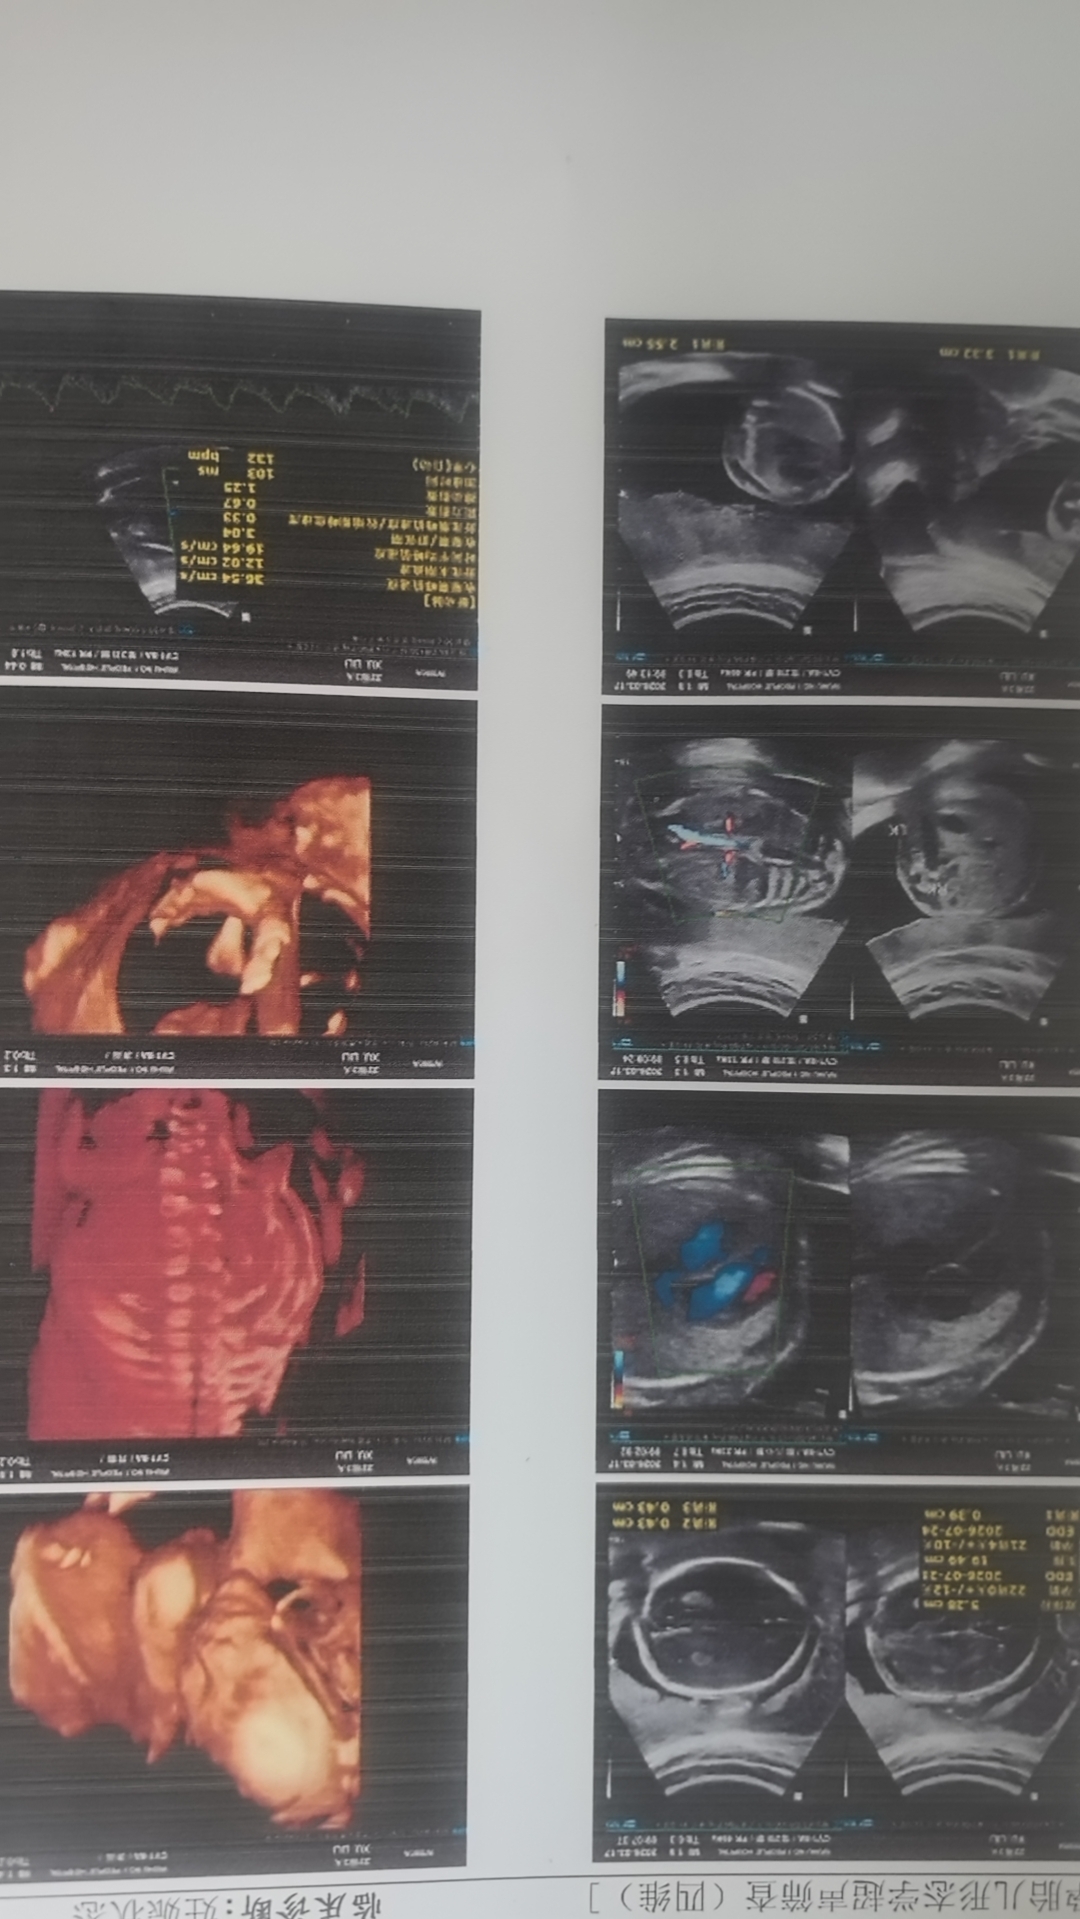

6点左右才轮到我,做的时候一直都很顺利,一开始就看到了宝宝的脸,医生赶紧就给拍下来,(前几个姐妹就是一直看不见脸)医生夸宝宝好看,后面做的也很顺利,说宝宝挺健康,都挺好的,出来的时候,没过的姐妹投来羡慕的眼光

到家里才拿出报告单,看了一遍,之前臀位,绕颈一周,今天胎位头位,也不绕颈了,老母亲也放心了